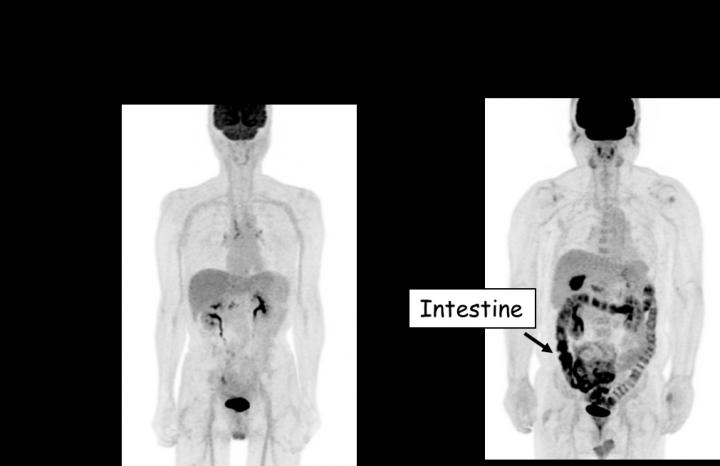

image: The areas where FDG (sugar) is accumulated appear black. In patients taking metformin (right), the intestine appears black, which indicates that FDG (sugar) is accumulated in the intestine.

Professor Ogawa's research team used PET-MRI to investigate the movement of sugar in the bodies of diabetic patients, both those who were taking metformin and those who were not. The team found that sugar (i.e. FDG) is heavily accumulated in the intestine of patients taking metformin (Fig. 1). To understand where in the intestine sugar accumulates, the research team subsequently investigated the "wall of the intestine" and the "inside of the intestine (stool and other contents)" separately using a special technique.

They found that, in patients taking metformin, more sugar was accumulated in the areas inside the intestine that are distal to the ileum (the anal side part of the small intestine) (Fig. 2). On the other hand, there was no difference in sugar accumulation in the "wall of the intestine" between patients who were taking and not taking metformin.

These results indicate that, when a patient takes metformin, sugar in the blood is released from the intestine into the stool. Not only the finding that metformin promotes the excretion of sugar into the stool, but also the revelation that sugar is excreted from the intestine into the stool itself are new discoveries that were not anticipated.

Previous studies using PET-CT showed that FDG was accumulated in the intestines of patients taking metformin. It was however assumed that FDG (sugar) was accumulated in the "wall of the intestine" without sufficient evidence because PET-CT cannot separately show the wall and the inside the intestine. In the current study, the new imaging technology PET-MRI allowed the research team to investigate the accumulation in the wall and the inside of the intestine (stool) separately, revealing for the first time that metformin-induced accumulation of sugar occurred exclusively inside the intestine.